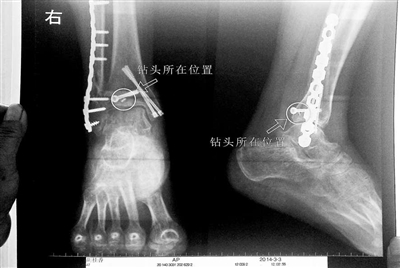

胡女士的腿部X光圖

看著X光片中自己腿內(nèi)的異物,胡女士就感到莫名的擔憂。胡女士于2013年3月在北京市豐臺區(qū)右安門醫(yī)院進行了一次骨折手術,術后醫(yī)生才發(fā)現(xiàn)手術時用來打眼用的鉆頭不慎遺留在了胡女士的骨頭中,并且無法取出。

近日,在豐臺區(qū)右安門醫(yī)院,北京青年報記者見到了胡女士,她走起路來顯得一瘸一拐,腿腳并不利索。在她帶來的X光片上,可以清晰地看到,有一個異物存在于腿內(nèi)部。

“我當時就嚇蒙了,怎么會有一個鉆頭在骨頭里?”胡女士余悸未消地說,第二天拍攝的X光片顯示,2厘米左右的鉆頭遺留在她右腳腳踝上部的骨頭內(nèi)。

胡女士說,當時旁邊的醫(yī)生勸慰自己,稱鉆頭留在腿里并不會有什么問題。出院后,胡女士每個月都會來醫(yī)院做復查,拍X光片。她說,每次都能夠清晰地看見自己骨頭里的那個明晃晃的“小東西”。

“留在她腿里的鉆頭確實無法取出。”徐主任解釋說,按常理說,鉆頭不應該斷在里面,但現(xiàn)在事情確實發(fā)生了。鉆頭沒有折在關節(jié),而是在跖骨內(nèi),跖骨主要起支撐作用,不像關節(jié)那樣起活動作用,而且這個部位比較質密,并非像肌肉要經(jīng)?;顒邮艿綌D壓。